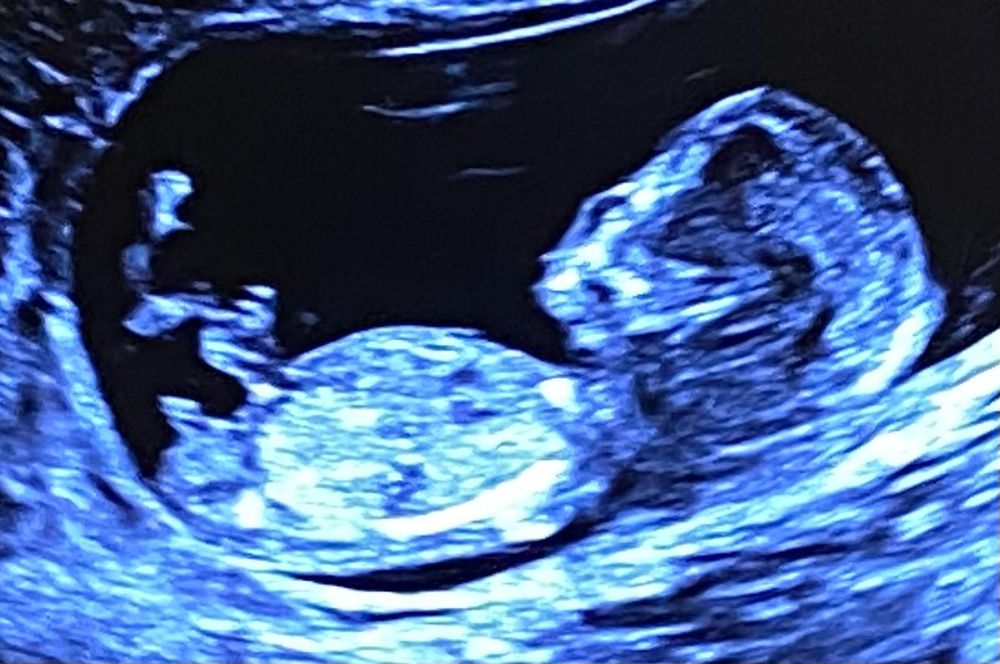

Пол по узи

У Вас фото, как будто показательное из интернета «Как определить мальчика» 😁 очень четко видно бугорок и он четко смотрит вверх. 100% мальчик, а если вдруг нет, я очень сильно удивлюсь .

Пацан 🧐😀

Мальчик💯

мальчик 100%

Мне кажется, это все-таки лобковая кость, а не орган, и поскольку не параллельно спинке, то мальчик

Мне кажется мальчик) вижу орган мужской😃

Эм.. Я вижу пипиську мужскую

Пистолет видно